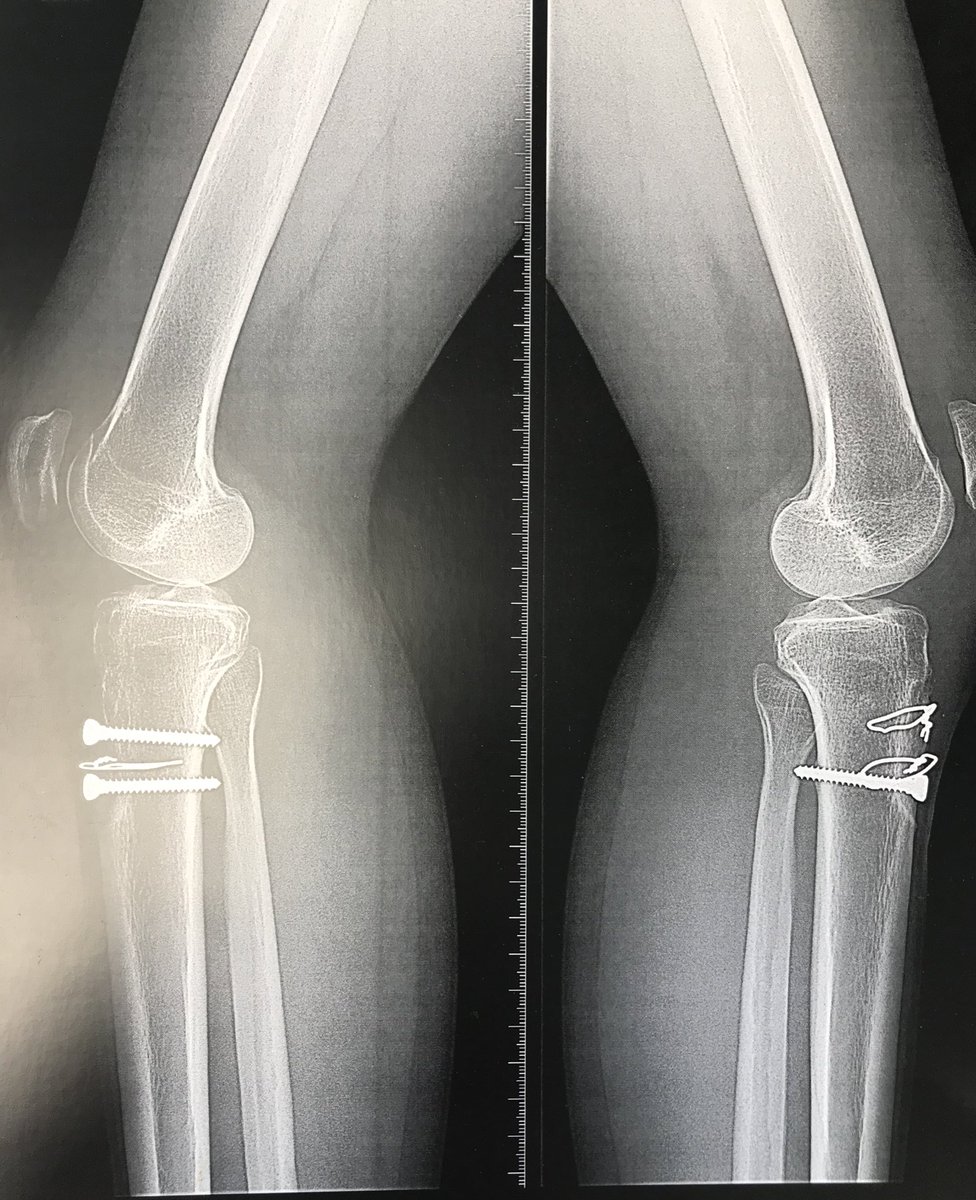

✅Poursuite des formations optimisation du parcours:

➡️WALANT